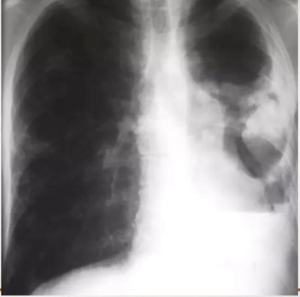

The most common abnormality in children is lymph node enlargement,

which is seen in 90-95% of cases.

10-year-old child with tuberculosis, shows widening of the right paratracheal stripe